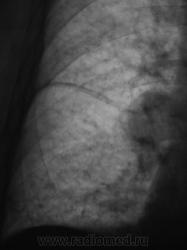

При расшифровке флюорограмм пациент "взят на контроль". Произведено стандартное дообследование.

Ваше мнение коллеги?

Здравствуйте Валентин Львович, не совсем понятно, где это по боковой проекции? В таких слчаях может помочь R-скопия лёгких, но право врача выбирать ту методику, которая ему ближе.

Здравствуйте Almo! Томограммы выполнены в стандартных срезах - 7, 9, 11 см.

Эта штучка неотделима от правой промежуточной артерии...